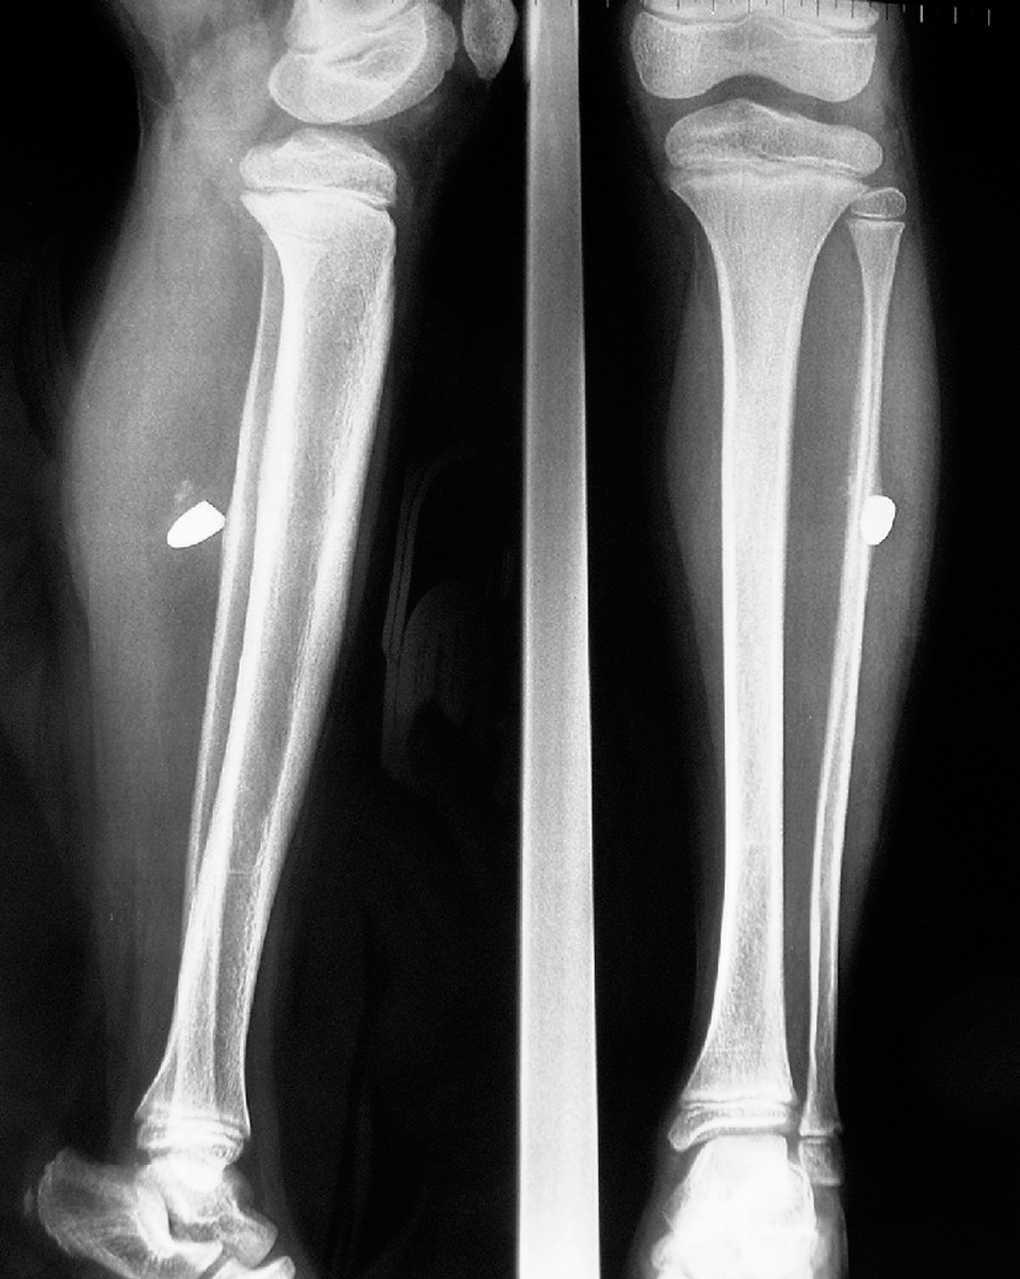

A la exploración se observó a nivel de la cara lateral externa de la pierna derecha, una induración delimitada, muy dolorosa a la palpación, sin presencia de síndrome compartimental y con movilidad y pulsos conservados. Cicatriz antigua (desde hace 2-3 años) en la cara interna del tercio superior de la pierna derecha, de origen desconocido. Se realizó una radiografía simple en la que se observó la presencia de un cuerpo extraño metálico, que se extrajo quirúrgicamente de forma programada, y que confirmó ser una bala (fig. 1). No se realizó determinación de la plumbemia. Un año después se encontraba asintomático. La familia no explicaba el hallazgo e insistía en la ausencia del niño en reyertas con armas de fuego en su país y afirmaban que no requirió ni recibió tratamiento médico alguno.

Figura 1. Radiología simple: cuerpo extraño metálico.